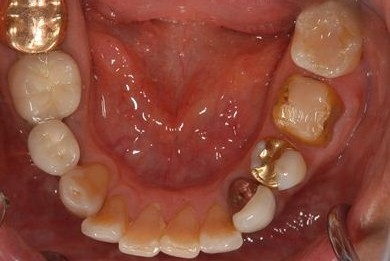

治療前

• 治療前